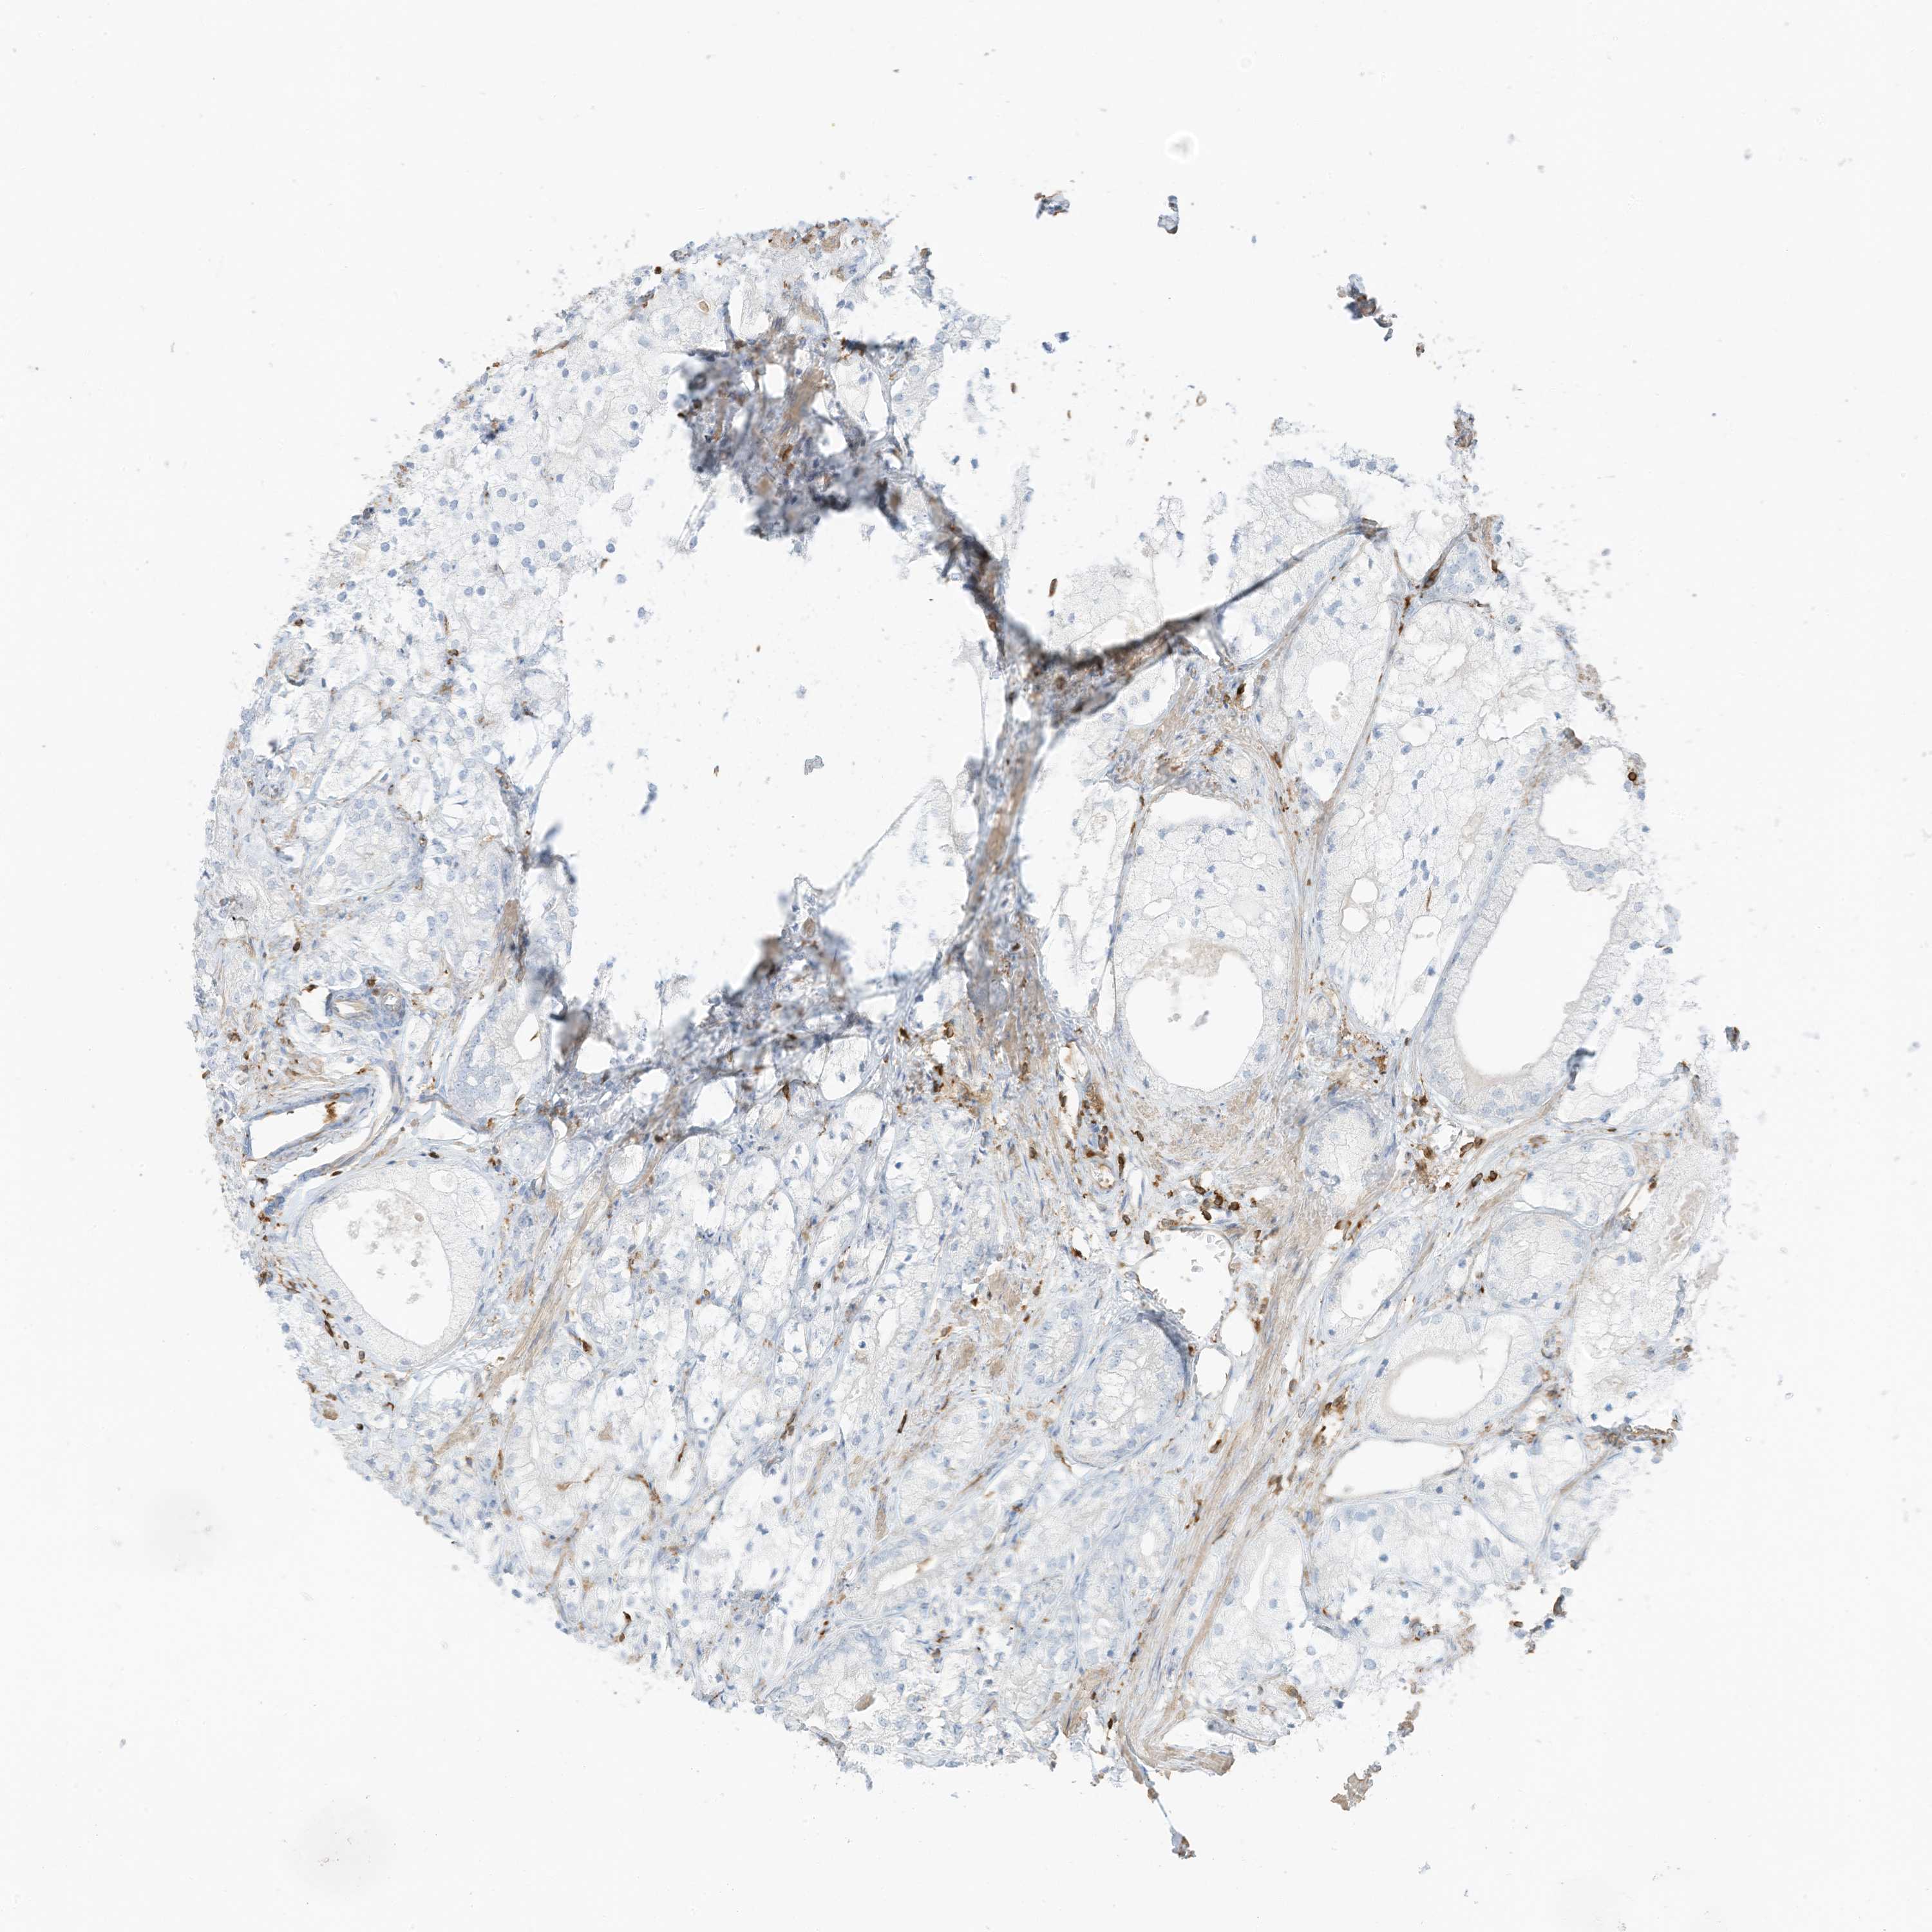

PROSTATE CANCER - Protein expressioni

A mouse-over function shows sample information and annotation data. Click on an image to view it in a full screen mode. Samples can be filtered based on level of antibody staining by selecting one or several of the following categories: high, medium, low and not detected. The assay and annotation is described here.

Note that samples used for immunohistochemistry by the Human Protein Atlas do not correspond to samples in the TCGA dataset.

Antibody stainingi

Antibody staining in the annotated cell types in the current human tissue is reported as not detected, low, medium, or high, based on conventional immunohistochemistry profiling in selected tissues. This score is based on the combination of the staining intensity and fraction of stained cells.

Each image is clickable and will lead to virtual microscopy that enables deeper exploration of all samples and also displays staining intensity scores, fraction scores and subcellular localization as well as patient and tissue information for each sample.

Antibody HPA035346

Antibody HPA061395

Staining

High

Medium

Low

Not detected

Intensity

Strong

Moderate

Weak

Negative

Quantity

>75%

75%-25%

<25%

None

Location

Nuclear

Cytoplasmic/membranous

Cytoplasmic/membranous,nuclear

Adenocarcinoma, NOS

Adenocarcinoma, High grade

Adenocarcinoma, Low grade